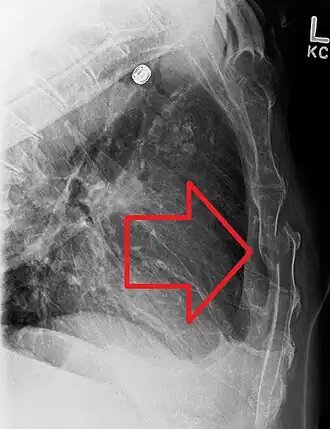

![]() Una fractura esternal desplazada | ||

En el diagnóstico se pueden utilizar las manifestaciones clínicas de una fractura, que incluyen: dolor, tumefacción, deformación, equimosis, inestabilidad y crepitación. Para confirmar el diagnóstico, se utilizan dos radiografías en distintos ángulos y TAC ( tomografía axial computarizada ).[5]